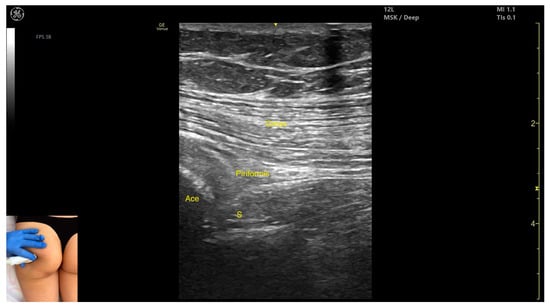

3.2.3. Key Ultrasound Landmarks

- Muscle morphology: It is part of the deep gluteal muscle group, along with the obturator internus, obturatorus externus, superior gemellus, inferior gemellus, and quadratus femoris.

- Muscle position: At this level, it appears as the first muscle mass superficial to the acetabular cortex. The sciatic nerve lies in close proximity, located deep to the piriformis.

- External fascia: It presents a well-defined fascia separating it from the gluteus maximus, which is important during botulinum toxin injection.

- Dynamic evaluation: During dynamic evaluation, scanning 2–3 cm distally toward the ischial tuberosity, the piriformis muscle tapers and disappears, and the obturator internus muscle becomes visible. Superficial to the obturator internus, the gluteus maximus and the sciatic nerve (within the intermuscular fascia) can be observed. Muscle contraction is visible during the external rotation and abduction of the femur at the hip joint.

| Piriformis | 8 cm lateral to sacrum; 10 cm proximal to the ischial tuberosity | Gluteus maximus (superficial); sciatic nerve (deep to muscle) | Transverse scan angled ~20° laterally toward the sacrum | Visualize piriformis and sciatic nerve; avoid nerve injury |